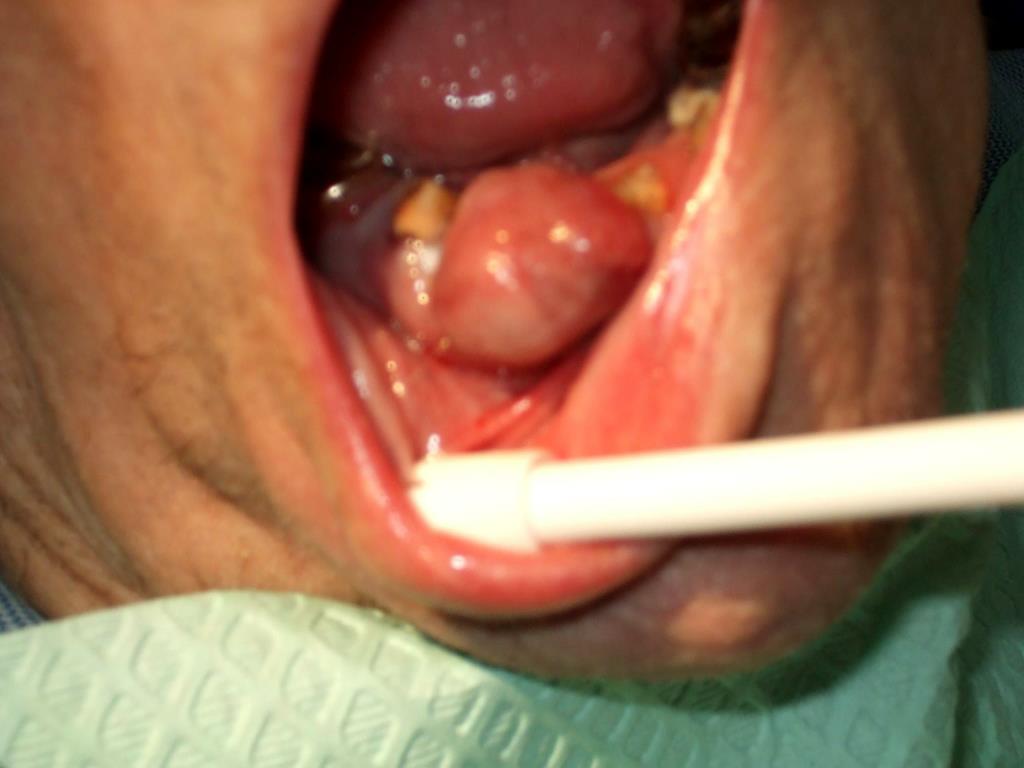

7. Patient stability in tolerating dental treatment in an office setting is of extreme importance and medical consults with the pt’s physicians are warranted. • In this way the dentist can be aware of medical conditions and polypharmacy that may require the need for antibiotic prophylaxis, cause bleeding issues, delayed healing time, overgrowth of oral tissue and increased caries risk.